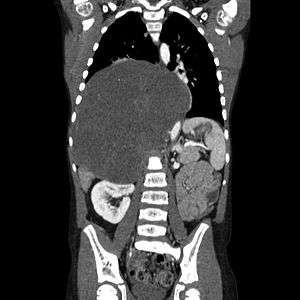

| CT scan of a large ganglioneuroma within the chest cavity | |

Ganglioneuromas can be diagnosed visually by a CT scan, MRI scan, or an ultrasound of the head, abdomen, or pelvis. Blood and urine tests may be done to determine if the tumor is secreting hormones or other circulating chemicals. A biopsy of the tumor may be required to confirm the diagnosis.[3]